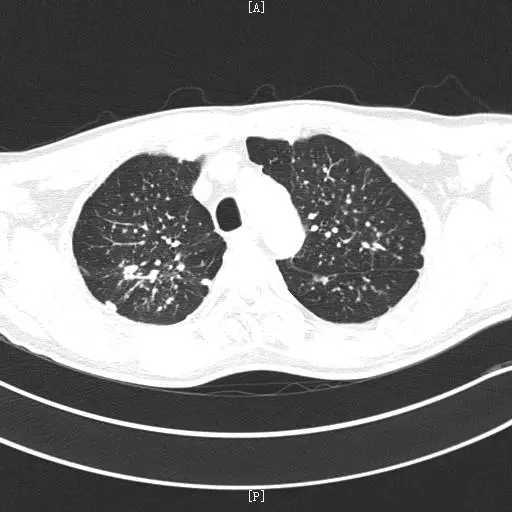

而尘肺的确诊,胸部CT是必不可少的一项检查项目。在CT上,尘肺主要表现为:双肺多发小结节影,结节直径一般小于10mm;除了小结节之外,还可能出现网格状影、蜂窝状影等等。它在肺上的结节常常分布不均匀,最开始主要是双肺上叶或者下叶背段,双肺下叶一般相对来说结节要少些,这也有助于它和急性粟粒型肺结核进行鉴别。除此之外,尘肺的结节常常密度比较高,还常常合并钙化灶。